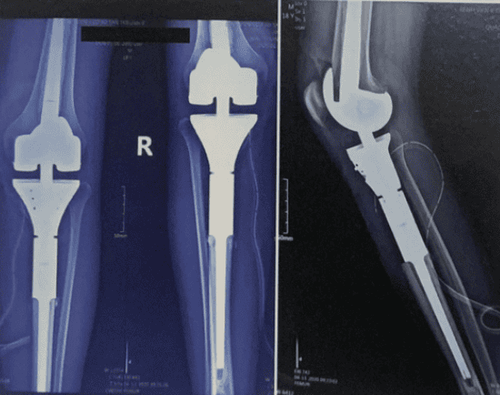

Để khắc phục vấn đề đó, với những tiến bộ gần đây trong thiết kế bộ phận giả, Prosthesis gắn kết mô-đun được sử dụng nhiều để tái tạo các khuyết xương ở đầu trên xương chày gần sau khi cắt bỏ khối u xương.

Việc thay khớp gối nhân tạo cùng đoạn xương chày bằng kim loại dạng mô-đun có những ưu việt nhất là trên những bệnh nhân :

- Có khả năng điều chỉnh độ dài khi chiều dài chân bệnh nhân phát triển dài hơn. Đảm bảo sự cân đối giữa 2 chân

Bệnh viện Vinmec đã thay hàng trăm ca thay khớp gối cùng đoạn xương chày megaprothesis cho các bệnh nhân ung thư trẻ em. Tại Vinmec áp dụng phương pháp chuyển vạt cơ và tái tạo điểm bám gân bánh chè.

Các bệnh nhân sau phẫu thuật phục hồi chức năng tốt, vận động, đi lại sớm. Không có trường hợp nào tái phát tại chỗ. Phần mềm tại chỗ tốt, không có biến chứng nhiễm trùng hay lộ khớp.